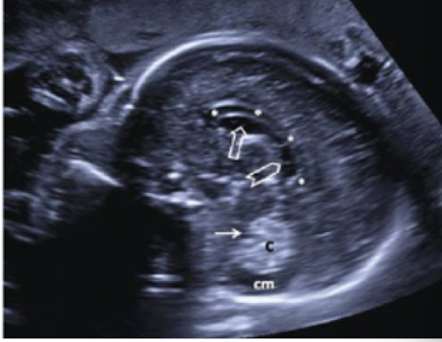

atrium

junction of the LV body, occipital, and temporal horns

located inferior to the mid skull

posterior/lateral to the thalamus and 3rd ventricle

usually filled with hyperechoic choroid plexus

measurement:

across posterior portion

posterior LV

less than 10mm is normal

Choroid plexus

located within the ventricles

produces CSF

appears hyperechoic